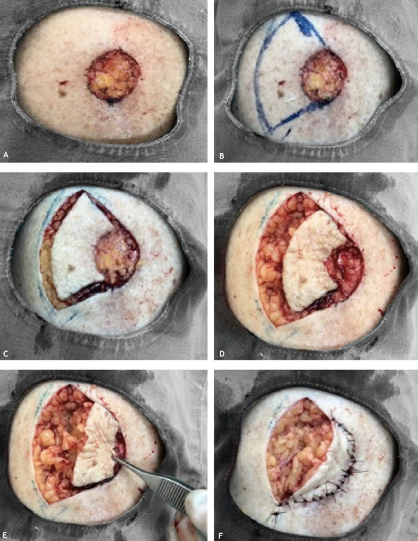

Paciente feminina, 92 anos, apresentando lesão nodular hiperceratótica de aproximadamente 2cm no maior diâmetro na face anterior da perna esquerda com biópsia evidenciando carcinoma espinocelular in situ (Figura 1), sem tratamentos prévios. Submetida à cirurgia micrográfica de Mohs, livre de tumor no primeiro estágio (Figura 2). Para fechamento primário, foi utilizada a técnica Keystone, com uma aba curvilínea de mesma largura do defeito e com ângulos de 90º nos cantos da área de exérese do tumor. Avançando a aba no defeito primário, resulta num defeito secundário que é mais longo e estreito. Perpendiculares ao avanço do retalho, as duas bordas periféricas foram avançadas em V-Y e a aba, avançada sobre o defeito, sendo suturado com fio nylon 4-0 (Figuras 3 e 4). A paciente apresentou boa evolução, sem complicações pós-operatórias (Figura 5).